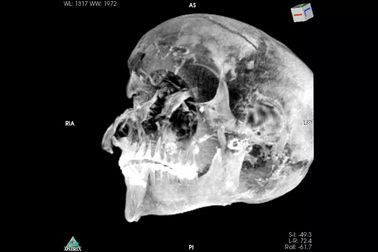

Xác ướp hé lộ pharaoh Ai Cập bị xử tử ngay trên chiến trườngPharaoh Seqenenre Taa II được cho là đã thua trận trên chiến trường, bị một toán quân thù tấn công bằng dao găm, rìu và giáo từ nhiều phía.